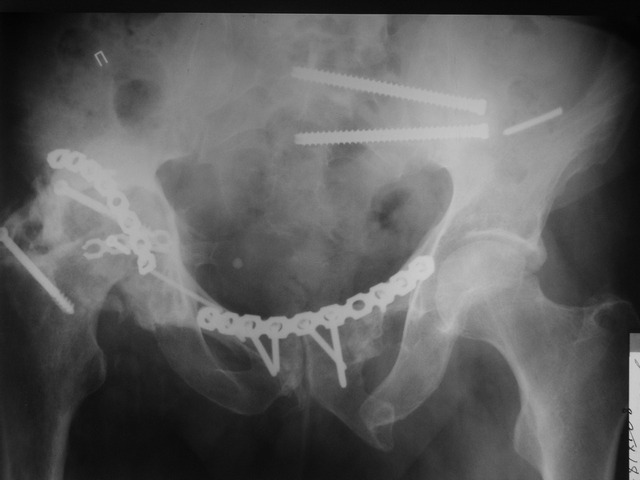

Пациент 49 лет, паровозная травма 23.2.2006, получил вертикальная нестабильное повреждение таза, разрыв левого крестцово-подвздошного сочленения, перелом лонной, седалищной костей слева, T-образный оскольчатый перелом правой вертлужной впадины с переломом заднего края, вывих правого бедра, посттравматическая пояснично-крестцовая плексопатия с обеих сторон, паралич мышц правой голени. В день травмы - вправление вывиха, скелетное вытяжение, 14.3.2006 чрескостный остеосинтез таза. 20.4.2006 остеосинтез правой вертлужной впадины пластинами, осложнившийся нагноением межмышечной гематомы правой ягодичной области. Получал консервативное лечение, было достигнуто полное заживление раны. 24.7.2006 введены илиосакральные винты слева. С декабря 2006 года и по настоящее время ходит на костылях без опоры на правую ногу. Планируется THA. Помогите определиться с вариантом костной пластики? И какую укрепляющую конструкцию использовать?